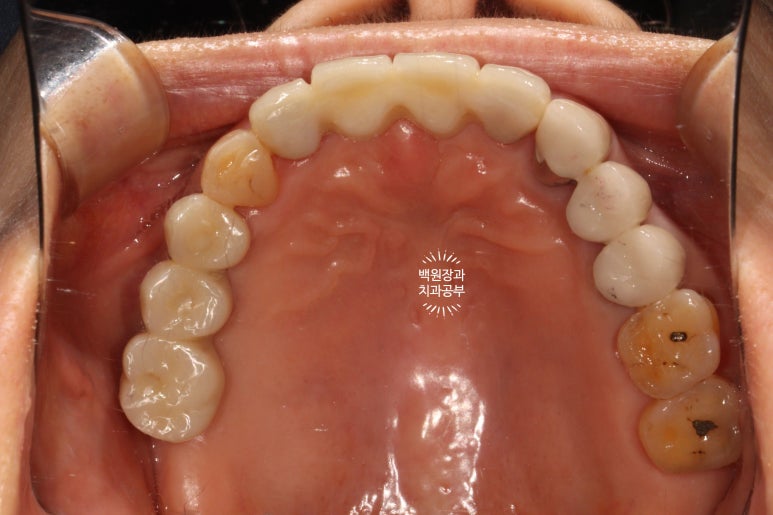

씹는면에서 보면 그 깔끔함이 더 두드러집니다.

좌측은 깔끔하게 마무리된 지르코니아 브릿지를 보실 수 있네요 :)

수술 전의 사진과 비교해서 생각보다 임플란트가 원래 자리와 비슷한 레벨에 위치해 있음을 확인할 수 있습니다.

이게 모두 임플란트 제거와 동시에 시행했던 덴티움 뼈이식재를 이용한 치조골 이식술 덕분입니다.